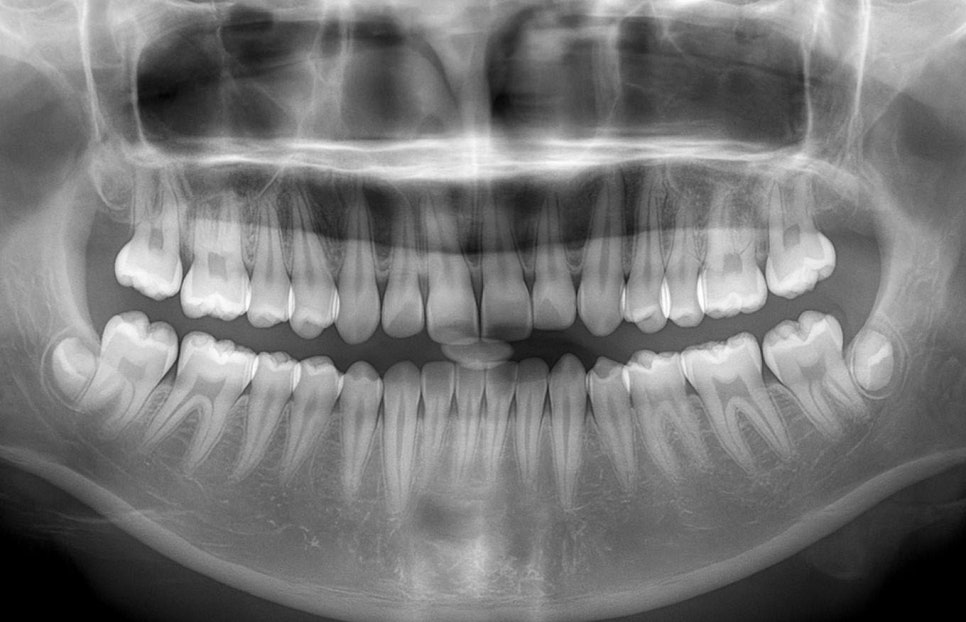

전체 구강을 한눈에 보고 싶을 때는

파노라마 엑스레이를 찍습니다.

이는 머리 주위를 돌면서 찍는 방식으로

모든 치아와 턱뼈 상태를 확인할 수 있으며,

사랑니의 위치나 턱관절, 부비동 질환도

같이 관찰할 수 있습니다.